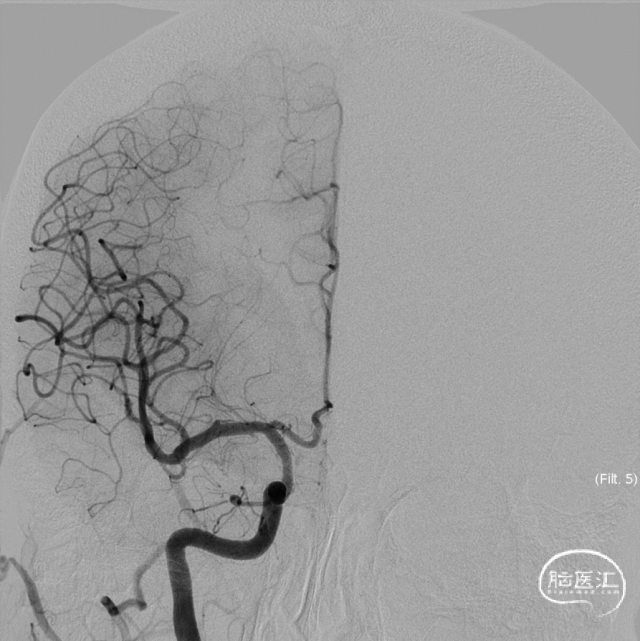

术前正侧位、3D、3D重建。

术后即刻造影、稀释造影:动脉瘤内造影剂滞留明显,支架贴壁良好,完全覆盖瘤颈。

术后3月复查,动脉瘤愈合良好,显影较前明显变淡。